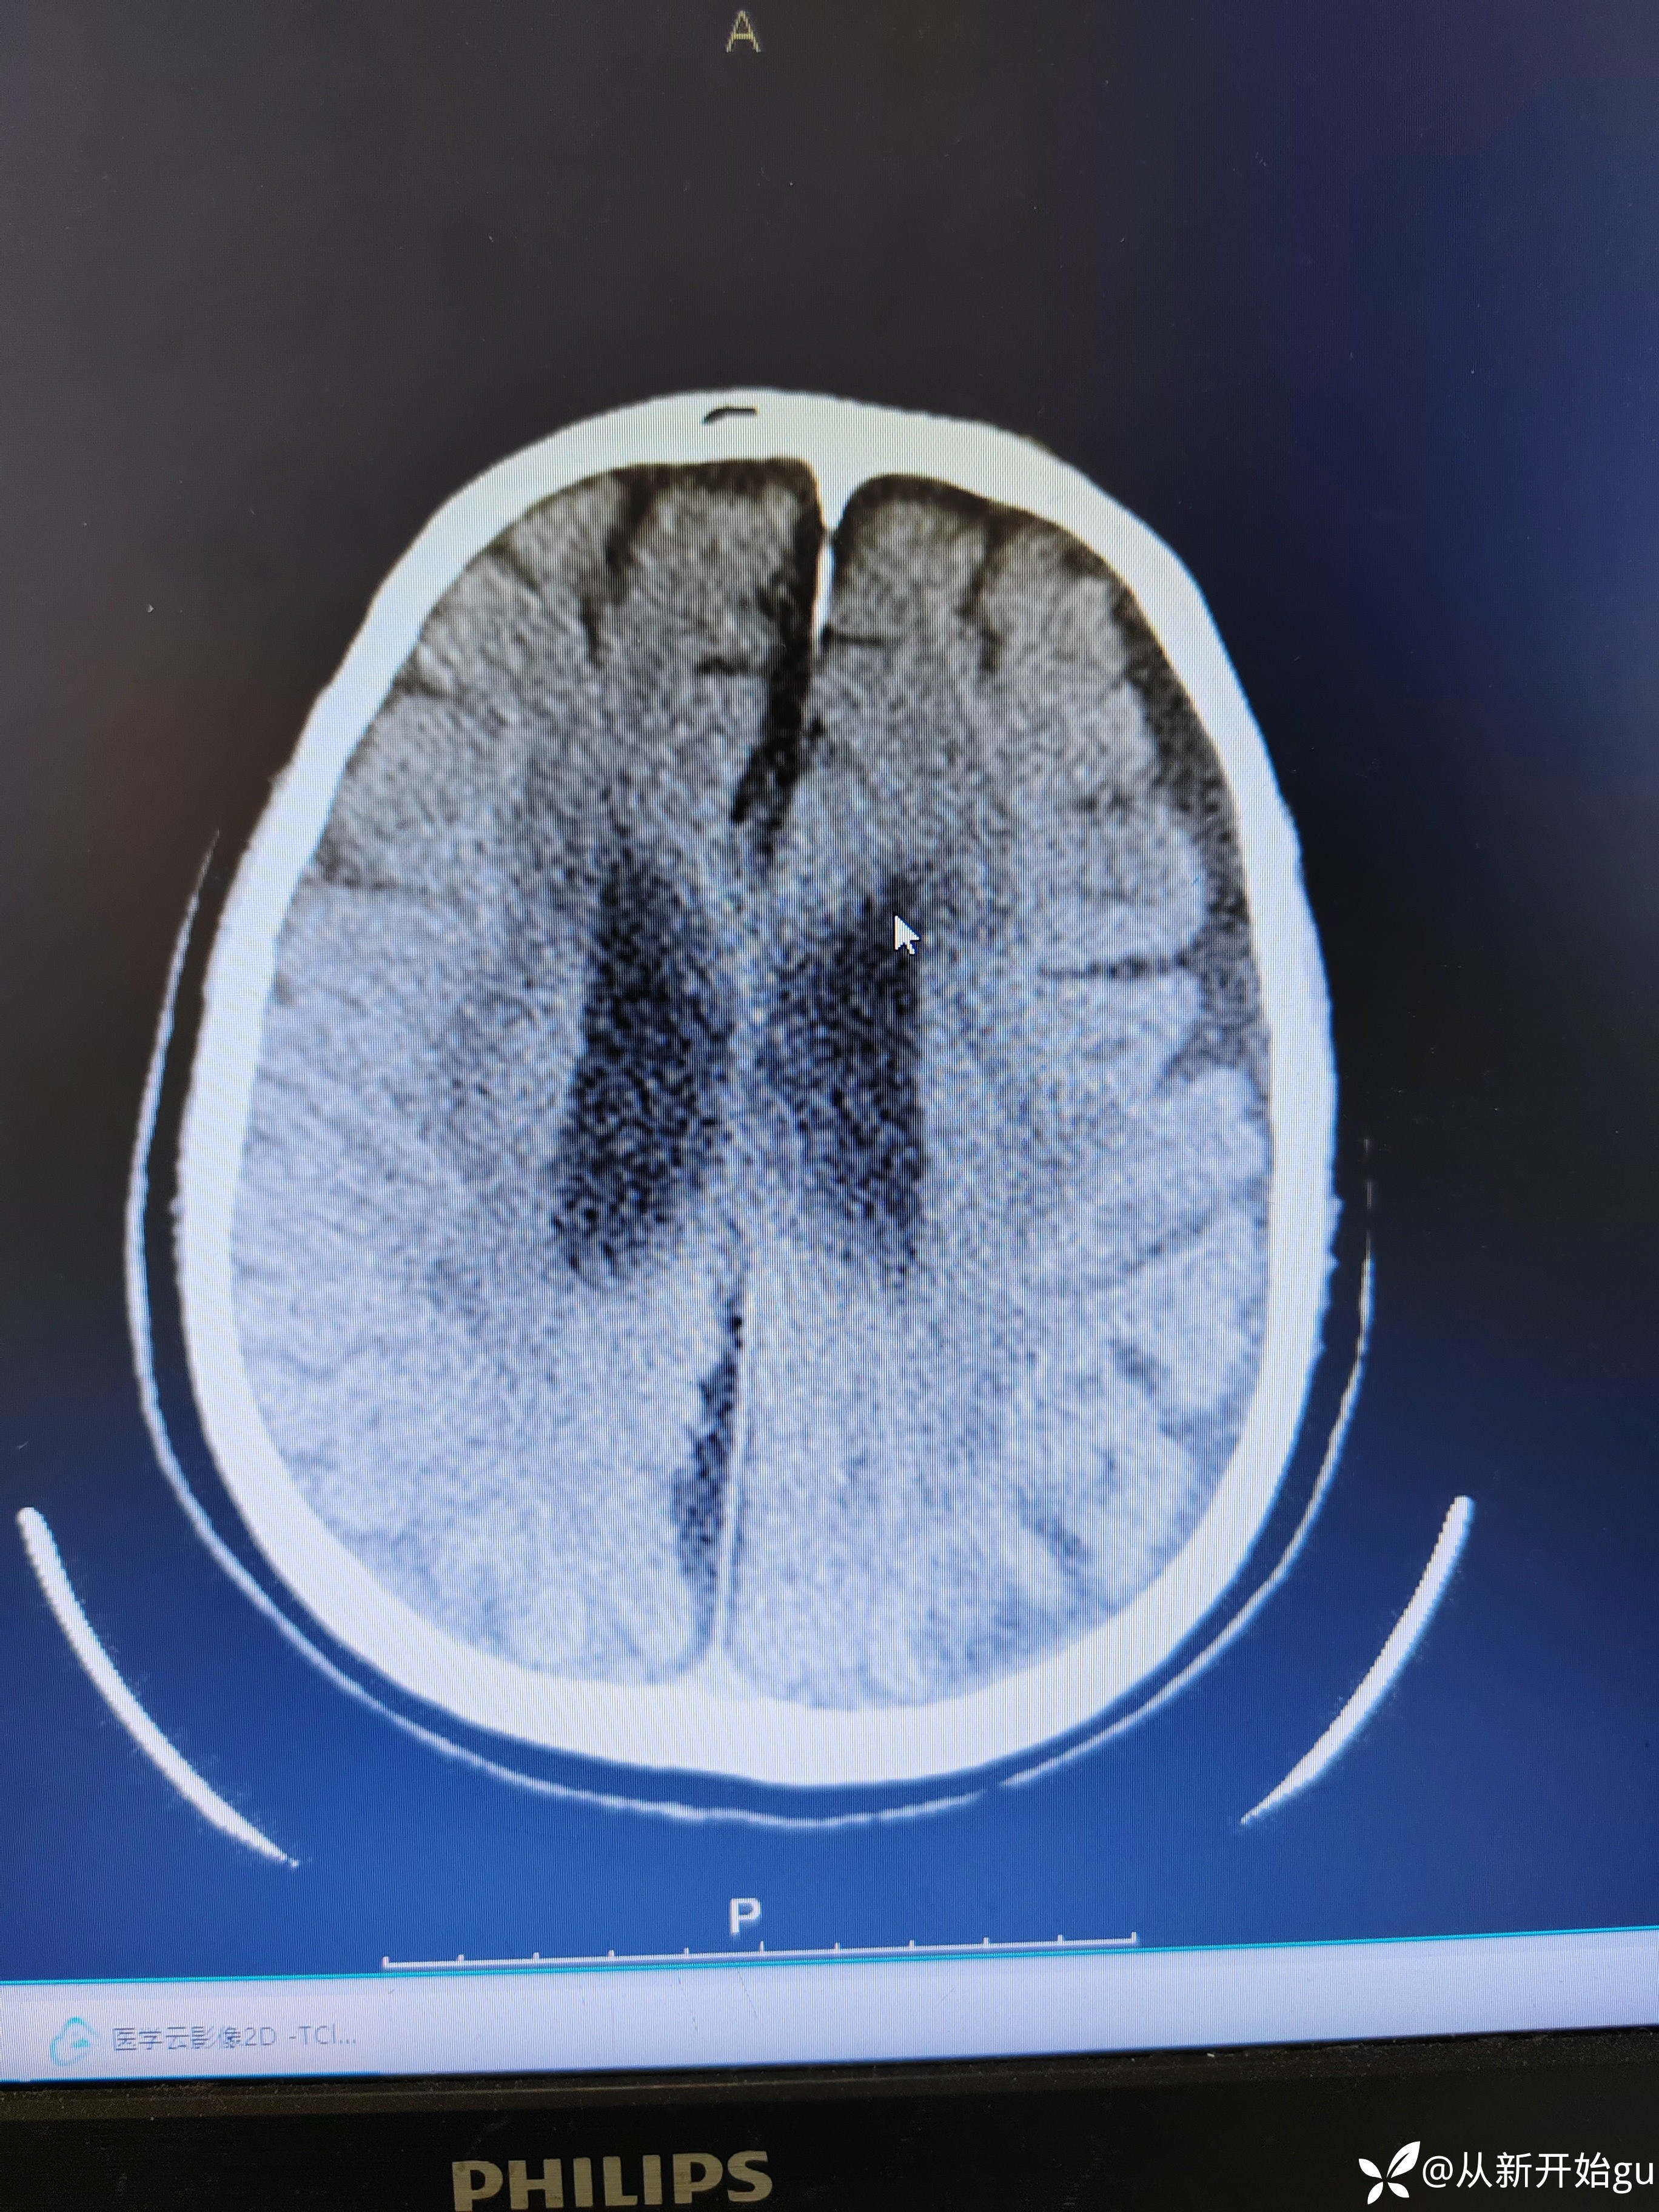

神经内外最近热帖已更新